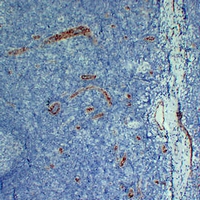

Immunohistochemical analysis of CD105 staining in human tonsil formalin fixed paraffin embedded tissue section. The section was pre-treated using heat mediated antigen retrieval with sodium citrate buffer (pH 6.0). The section was then incubated with the antibody at room temperature and detected using an HRP conjugated compact polymer system. DAB was used as the chromogen. The section was then counterstained with haematoxylin and mounted with DPX.